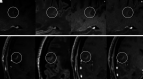

Background and purpose: We hypothesized that 3D T1-TSE "black-blood" images may carry an increased risk of contrast-enhancing lesion misdiagnosis in patients with MS because of the misinterpretation of intraparenchymal vein enhancement. Thus, the occurrence of true-positive and false-positive findings was compared between standard MPRAGE and volumetric interpolated brain examination techniques.

Results: The intraparenchymal vein contrast-to-noise ratio was higher in SPACE than in MPRAGE and volumetric interpolated brain examination images (P < .001, both). There were 66 true-positives and 74 false-positives overall. SPACE detected more true-positive and false-positive results (P range < .001-.07) but did not increase the patient's true-positive likelihood (OR = 1 1.29, P = .478-1). However, the false-positive likelihood was increased (OR = 3.03-3.55, P = .008-.027). Venous-origin false-positives (n = 59) with contrast-to-noise ratio and morphology features similar to small-sized (≤14 mm3 P = .544) true-positives occurred more frequently in SPACE images (P < .001).

Conclusions: Small intraparenchymal veins may confound the diagnosis of enhancing lesions on postgadolinium black-blood SPACE images.